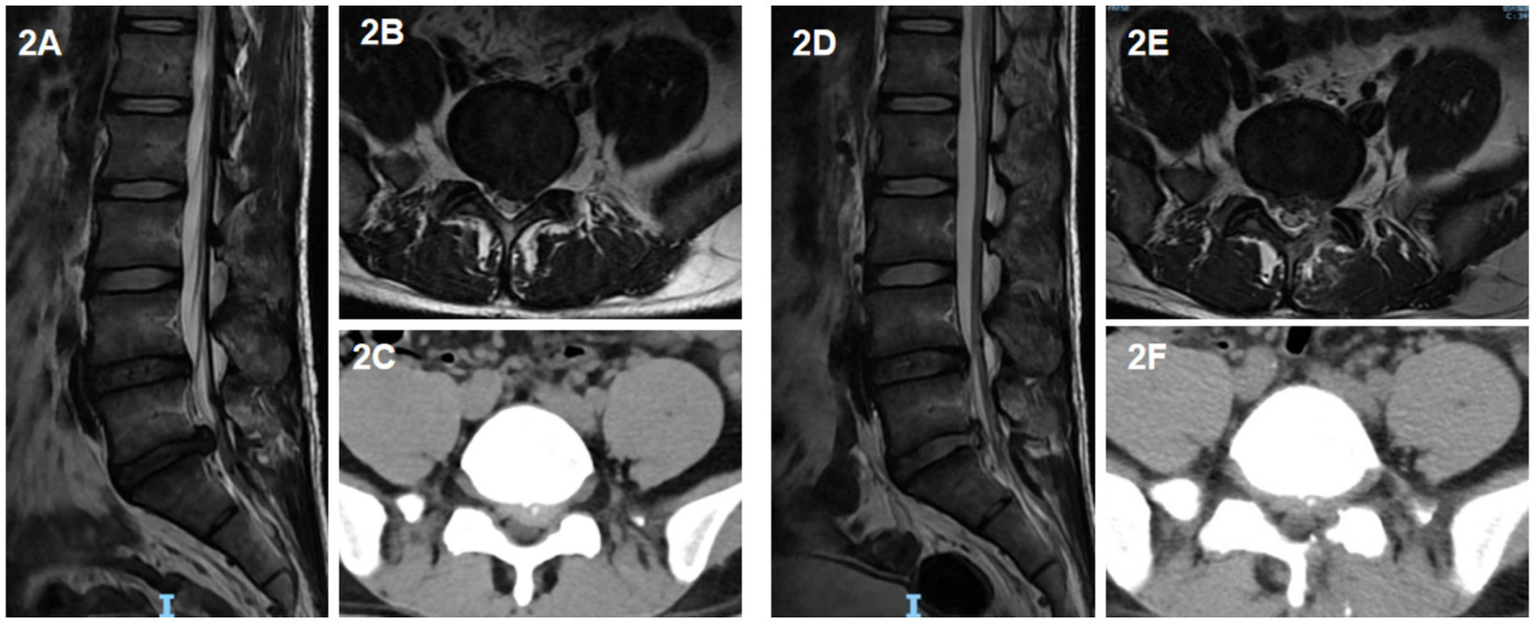

UBE surgery: the dual channels were located on the medial side of the upper and lower pedicle lines. A horizontal transverse line was made for the intervertebral space of the responsible segment. The horizontal transverse line and the intersection point of the medial pedicle line 15 mm at the head end and 15 mm at the tail end were double channels. One channel is the endoscopic observation channel, and the other side is the operation channel. The positions of the two channels could be changed according to the situation. The skin and deep fascia were incised at the double channel, and the cannula was placed at the junction of the spinous process and laminae. Soft tissue dilation and muscle dissection were performed, endoscope and working channel were inserted, respectively. Then the endoscope was connected, the electrocoagulation knife stopped the bleeding, and the nerve root stripper carefully revealed the nerve root. After the nucleus pulposus protrusion and part of the nucleus pulposus in the intervertebral disc were removed by the nucleus pulposus forceps under the endoscope, another exploration was conducted to confirm that there was no significant residual nucleus pulposus tissue in the spinal canal and the nerve root decompression was complete. Under the endoscope, the dural sac was seen to pulsate with respiration, and the annulus fibrosus was formed using radiofrequency knife. After completion, the examination was conducted again. If there was obvious bleeding, radiofrequency knife was used to stop bleeding under the endoscope. Finally, the endoscope and working channel were exited, and the suture orifice after the negative pressure drainage tube was indwelled to end the operation (Figure 2).

Figure 2

A 39-year-old male patient with left-sided protrusion of the L5/S1 intervertebral disc who underwent UBE surgery. (A) Sagittal view of preoperative lumbar MRI; (B) horizontal view of preoperative lumbar MRI; (C) Horizontal view of preoperative lumbar CT; (D) sagittal view of postoperative lumbar MRI; (E) horizontal view of postoperative lumbar MRI; (F) horizontal view of postoperative lumbar CT.